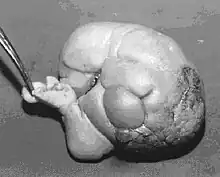

Ocurre en 1 de 1 000 000 nacimientos,[1][2] y se define como una masa fetiforme totalmente encerrada dentro del cuerpo del autósito o hermano desarrollado. Al extraerse, está envuelto en lo que parece un huevo de gallina, pero mucho más grande y extremadamente duro. El parásito, cuando es extraído y expuesto, tiene un color blanco. Una vez que se extrae, muere, ya que es un tejido totalmente dependiente de su hospedador. Al igual que en los gemelos parásitos, corazón y cerebro están ausentes o son muy rudimentarios. Puede estar más o menos organizado, con características muy variables, desde apenas una bola de tejidos hasta contener restos de pelo, hueso, manos con dedos y uñas y hasta piernas. La extirpación quirúrgica no presenta el menor problema dado que no pasan de ser tumores que pueden llegar a ser un potencial riesgo para su hospedador, debido a que se alimenta de este, representando para el hospedador una carga semiviva sin función en el organismo, y pueden llegar a malignizar.[3]